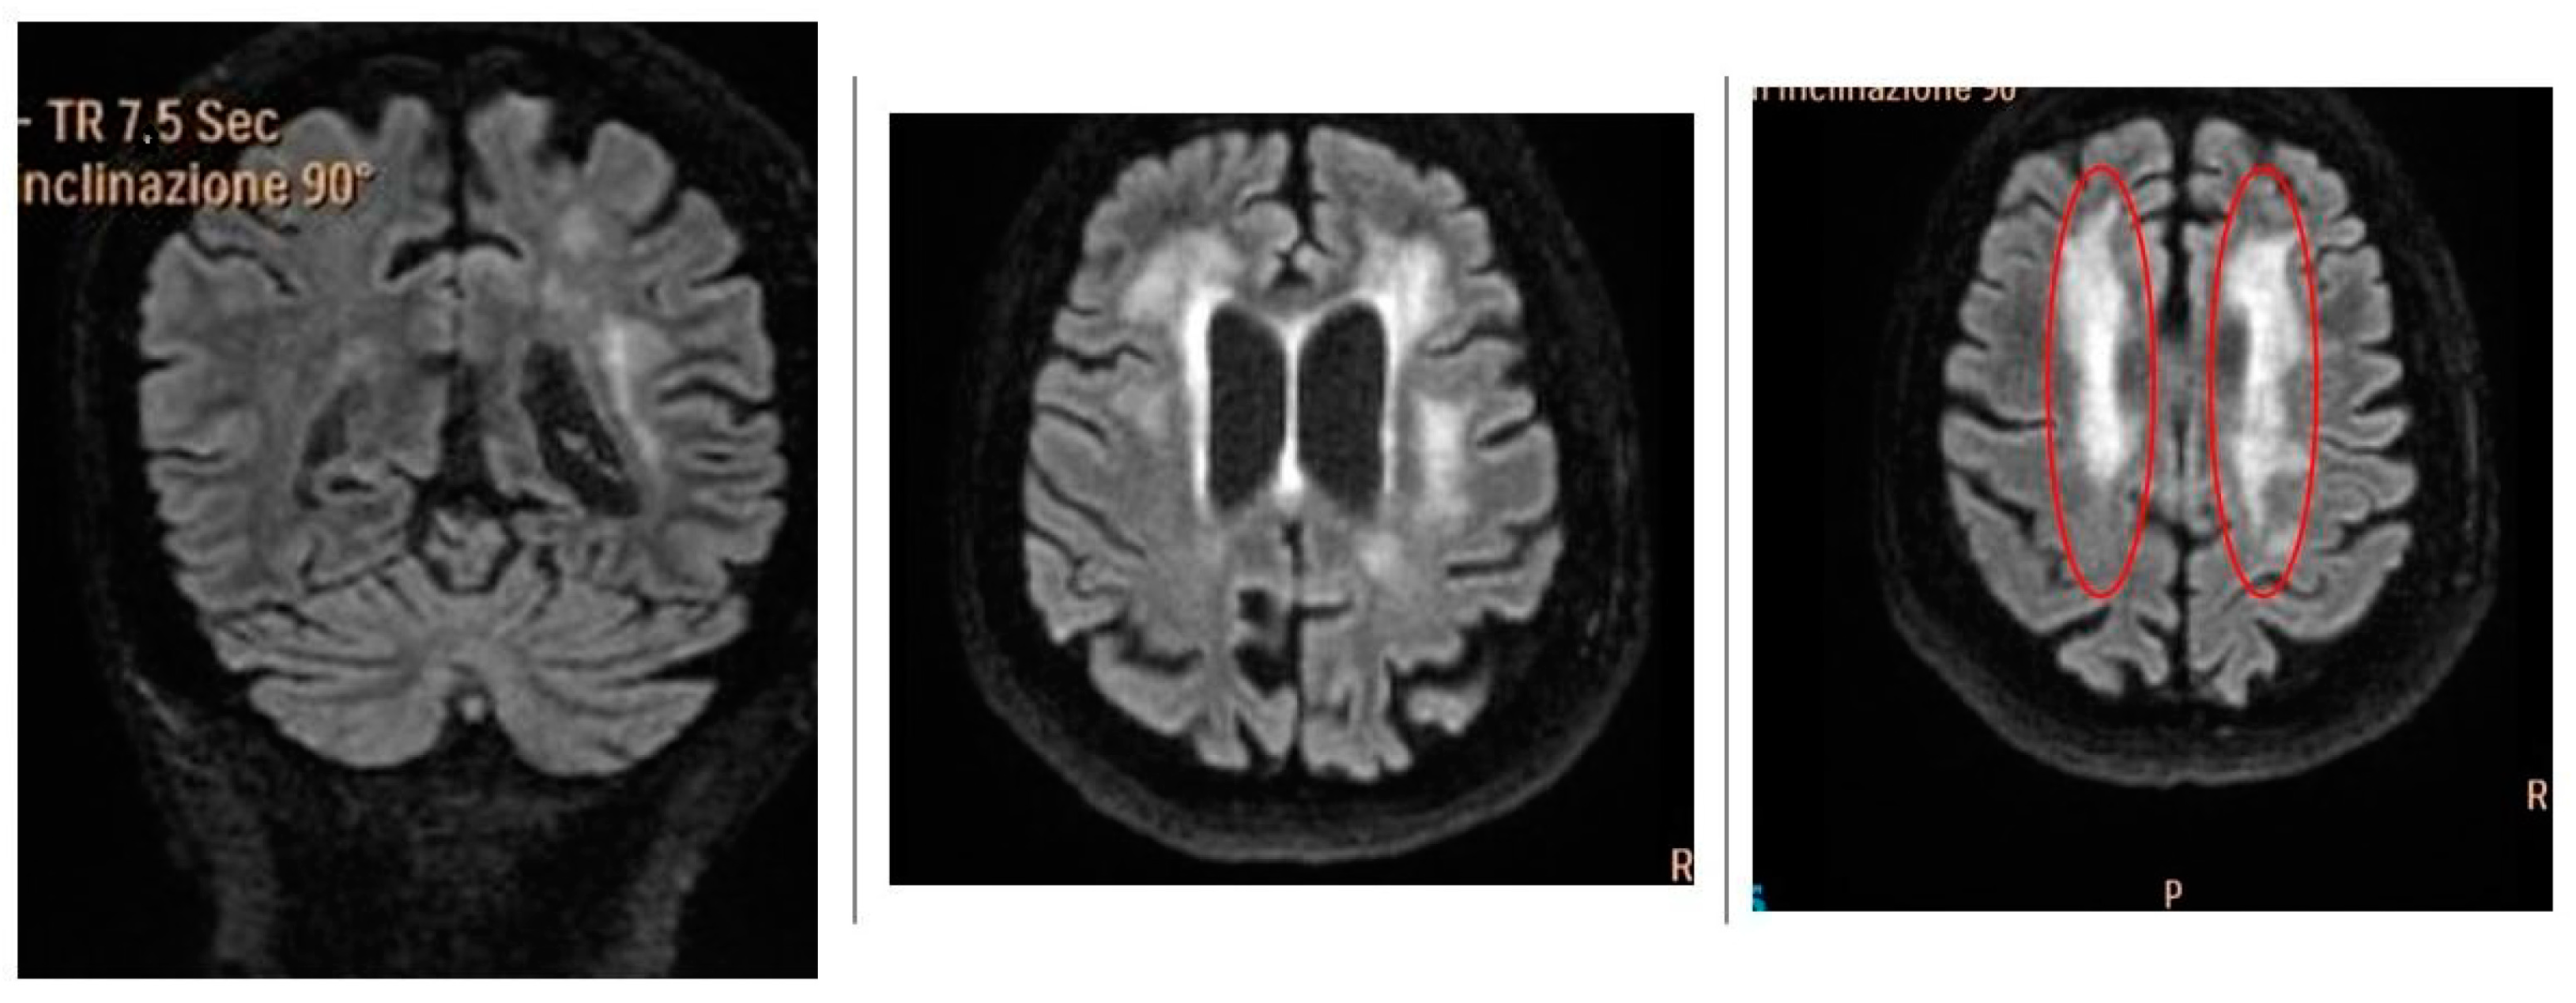

2.3.1. Patient 1

2.3.2. Patient 2